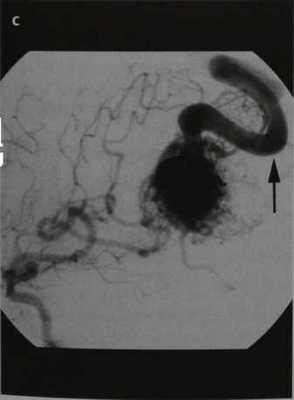

Пиальная артериовенозная мальформация головного мозга . МРТ, Т2-ВИ в аксиальной плоскости (а, b). ДСА в боковой проекции после введения КС в правую внутреннюю сонную артерию (с). Тубулярное отсутствие сигнала от потока в очаге АВМ (черные стрелки) на Т2-ВИ (а). Гипоинтенсивная гематома на Т2-ВИ (дезоксигемоглобин; а, белые стрелки).

Тубулярное отсутствие сигнала на поверхности головного мозга (вена; b, стрелка).

Определяется раннее контрастное усиление поверхностной мозговой вены, начинающейся от ветвей средней мозговой артерии (с, стрелка), и виден располагающийся между ними клубок сосудов (очаг, с)